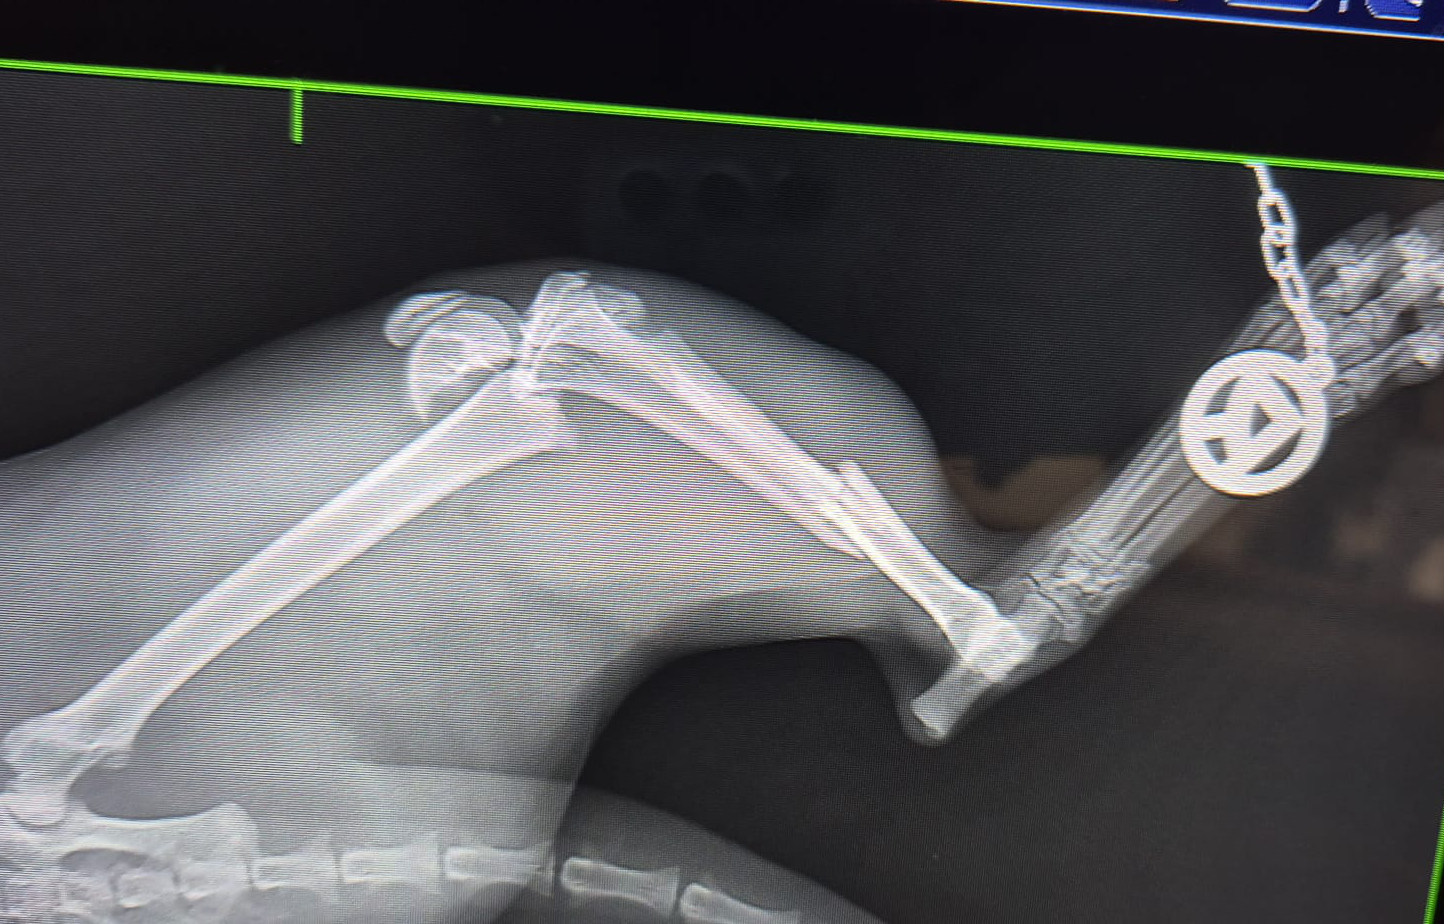

Aktuell wurde vom Tierheim eine Dame unterstützt, deren Kater einen komplizierten Beinbruch hat. Wenn das Tierheim nicht geholfen hätte, wäre der Kater nicht mehr am Leben. Er hat die Op gut überstanden und hat noch ein schönes Leben vor sich.